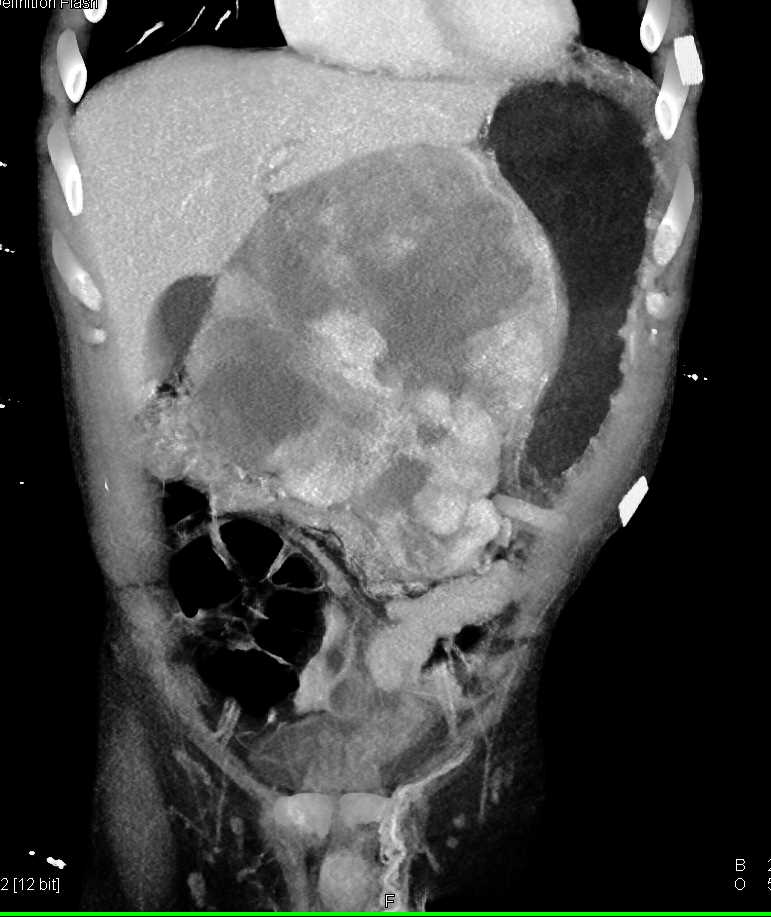

Lagre Gastric GIST Tumor